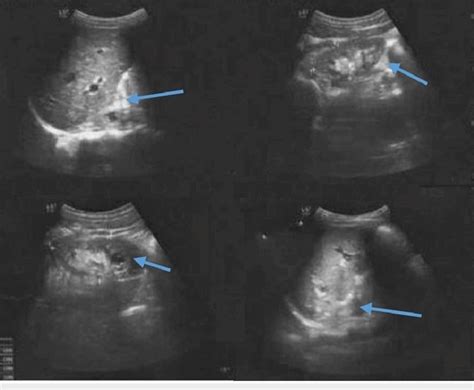

C2348956) a description of heterogeneous density elements seen in a tissue composition image obtained by sonography. Web “heterogeneity” by the word only it is quite understandable that it means something which is not uniform. Web a heterogeneous liver appears to have different masses or structures inside it when imaged via ultrasound. A heterogeneous, normal sized thyroid may not mean much, or it could indicate one of a number of inflammatory/infiltrative processes i.e. Web echotexture is the characteristic pattern or structure of the tissue layers as seen during ultrasonic imaging. David sneid answered endocrinology 43 years experience it. Web heterogeneous is a word pathologists use to describe tissue that looks very different from one area of the tissue to the next. Differences in colour, shape, and size. For example, a dermoid cyst has. 1 doctor answer • 1 doctor weighed in dr.

Web a heterogeneous liver appears to have different masses or structures inside it when imaged via ultrasound. Web what is heterogeneous echotexture the echotexture of a nodule can be heterogeneous or homogeneous. Web heterogeneous echotexture (concept id: Web what is thyromegaly with heterogeneous echotexture mean? Web heterogeneous refers to a structure with dissimilar components or elements, appearing irregular or variegated. It simply means that the uterus is not totally. Differences in colour, shape, and size. So in this case it is the thyroid. 1 doctor answer • 1 doctor weighed in dr. With heterogeneous, the enlarged and affected. Web heterogeneous is a word pathologists use to describe tissue that looks very different from one area of the tissue to the next.